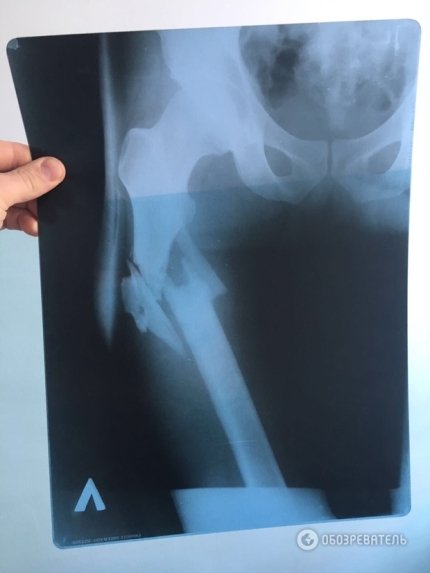

В то же время, было опубликовано фото рентгеновского снимка простреленной ноги пострадавшего и пулевых отверстий на его штанах.

Учитывая положение входного и выходного отверстий от пули, можно предположить, что пуля шла сверху вниз. О том же свидетельствует рентгеновский снимок, где видно, что обломки кости смещены вниз от таза.

По характеру пулевого ранения в ноге мужчины, у которого произошел конфликт с Пашинским, можно сделать вывод, что депутат стрелял не из положения лежа, а сверху вниз.

Таким образом, слова Пашинского о том, что он выстрелил из положения лежа в стоящего мужчину, выглядит неправдоподобной.